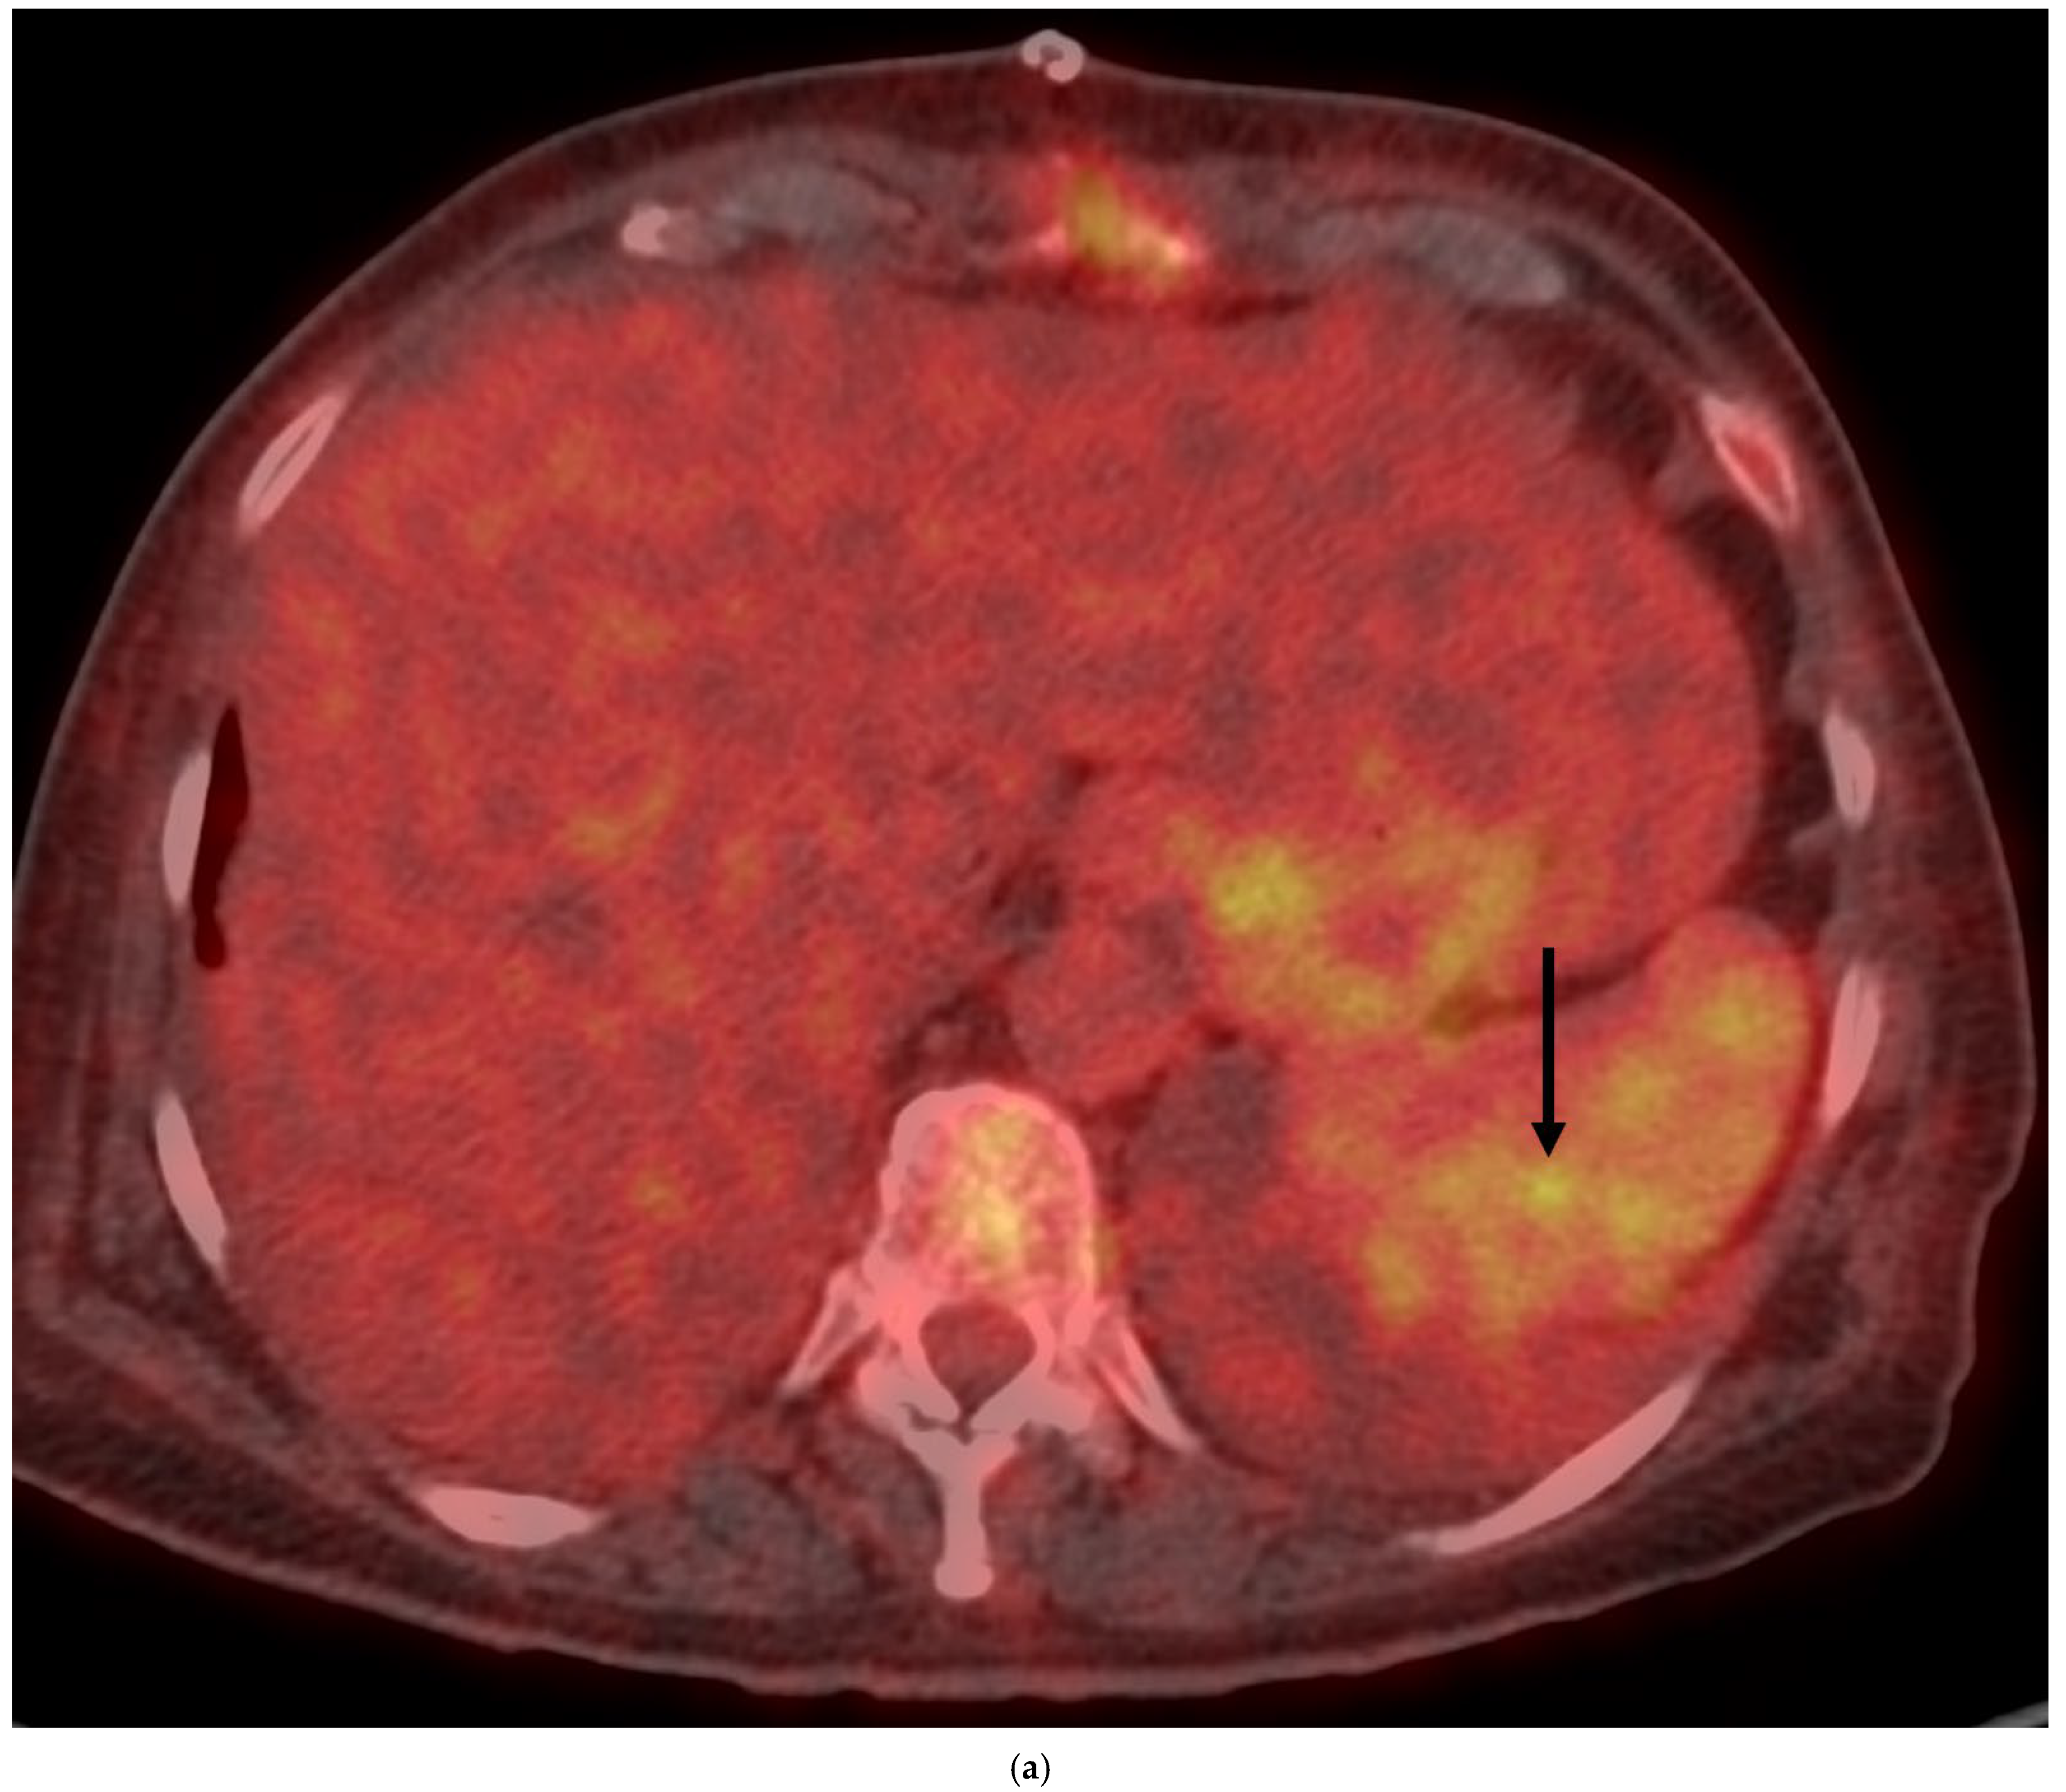

4. Clinical Characteristics of VIAs-Patients